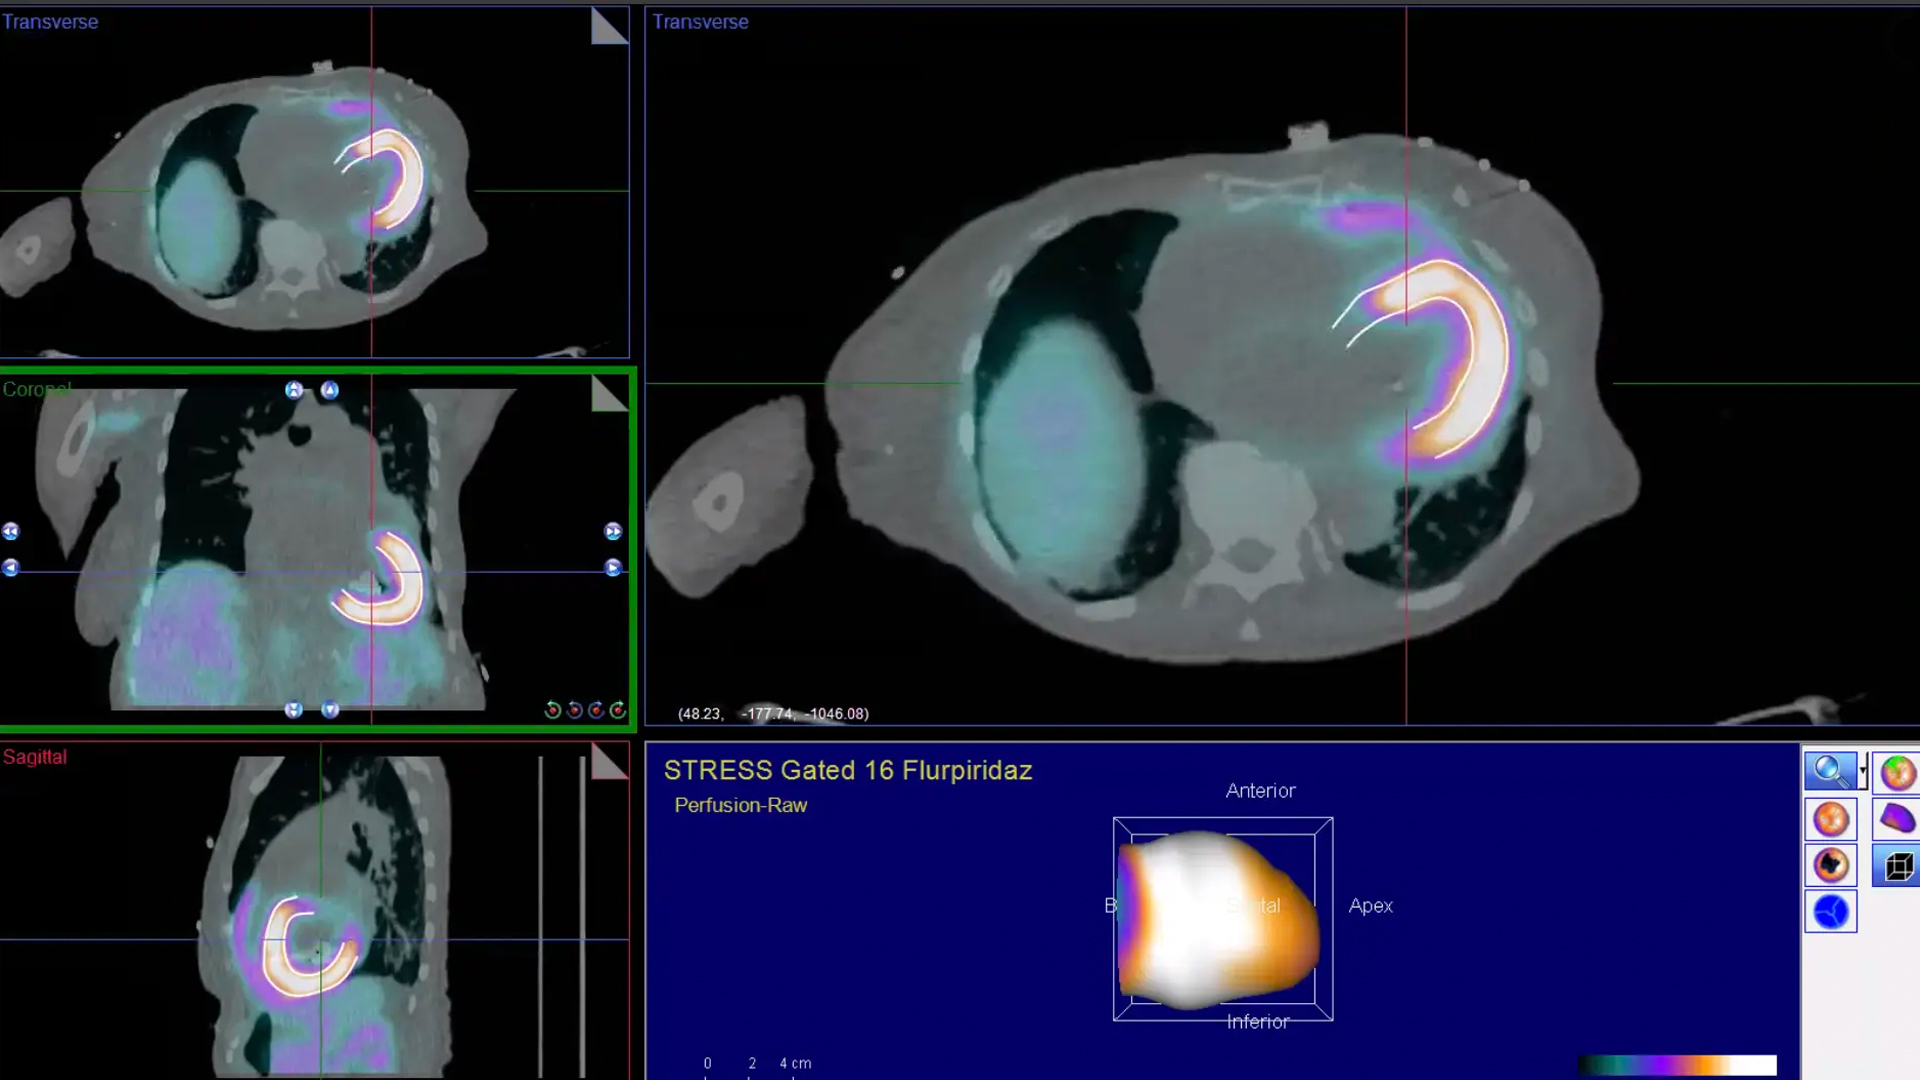

Imaging Highlights